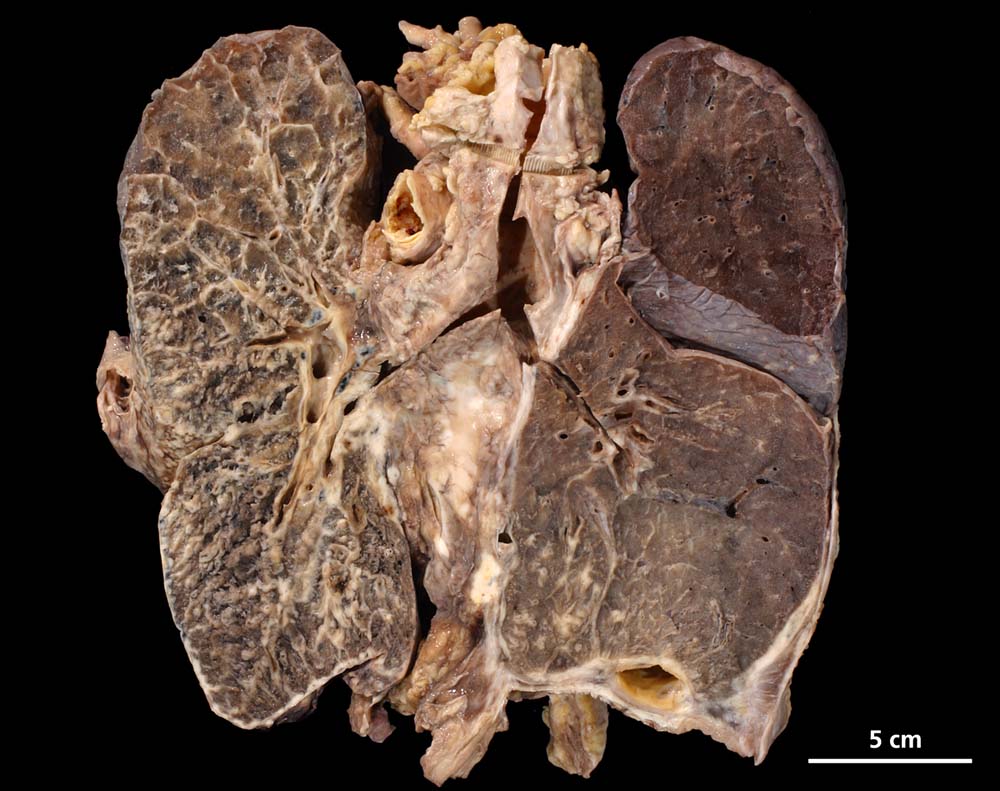

Das metastatische Wachstumsmuster von primären Bronchuskarzinomen und extrapulmonalen Tumoren innerhalb der Lunge ist variabel. Hämatogene Metastasen imponieren makroskopisch als multiple scharf begrenzte rundliche Knoten in allen Lappen meist in peripherer Lage. Der metastatische Befall von Lymphknoten kann durch direkte Tumorinfiltration durch den Primärtumor erfolgen (=per continuitatem) oder über die Lymphgefässe. Bei einer ausgeprägten lymphogenen Tumorausbreitung erscheinen subpleurale mit Tumor gefüllte Lymphgefässe makroskopisch als prominente weisse Streifen. Mikroskopisch lassen sich Tumorinfiltrate in peribronchialen und perivaskulären Lymphgefässen nachweisen (=Lymphangiosis carcinomatosa). Hepatozelluläre Karzinome metastasieren typischerweise in Form von Tumorembolien (> 1279) hämatogen in die Lunge.

• Sternförmiges Karzinom mit zentraler Vernarbung mit reichlich schwarzem Anthrakosepigment.

• Das Karzinom ist aufgebaut aus tubulären und kribriformen Drüsen.

• In den sternförmigen Ausläufern finden sich erweiterte Endothelausgekleidete Lymphgefässe in der Nachbarschaft von Blutgefässen.

• Die erweiterten Lymphgefässe enthalten solide Tumorzellaggregate.

• Vermehrte Alveolarmakrophagen in den peritumoralen Alveolen mit phagozytiertem Anthrakose- und Hämosiderinpigment (Rauchermakrophagen).

• Peritumorales Lungenemphysem (Traktionsemphysem).